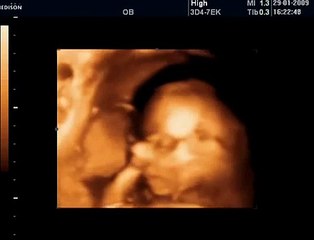

31 Haftalık Gebelik Bebek Ultrason Görüntüsü

Hafta hafta gebelik dönemi 31 haftalık bebek ultrason görüntüsü. Gebelikte 31. hafta daha çok bilgi için sayfamızı ziyaret edebilirsiniz.